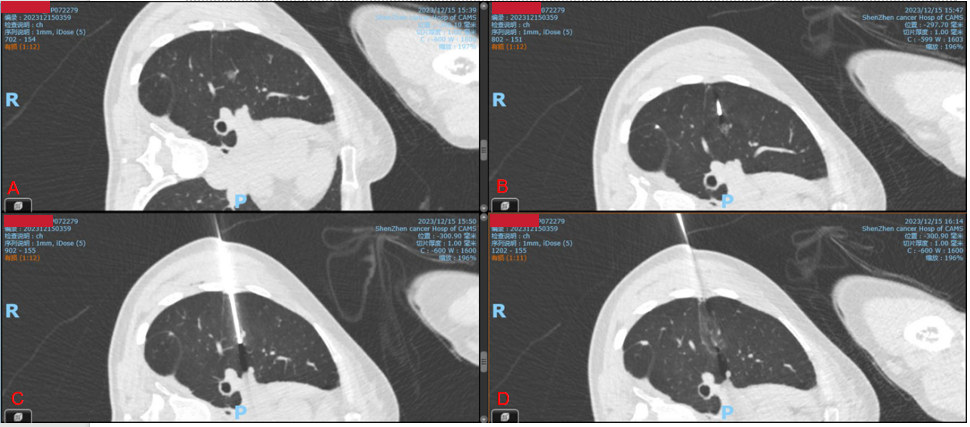

选择合适体位进行局部麻醉,在CT辅助下置入射频消融针,精准定位到结节结节所在处——右中肺进行热消融。将近30分钟,第一个结节顺利完成消融。采取同样的办法,处理右肺上叶结节。

图A:右肺中叶混合磨玻璃结节,直径9mm,CT考虑肺癌

图B:消融针穿刺肺结节过程

图C:消融针穿过结节中心

图D:形成典型的“煎蛋”征像,标志着肺结节完全消融。

图为杨成林正在进行CT引导下的肺肿瘤热消融术治疗术